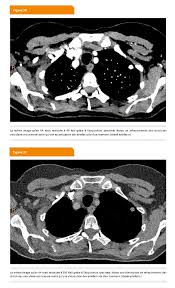

Infection Au Covid 19 Quelle Imagerie Le Generaliste

Infection Au Covid 19 Quelle Imagerie Le Generaliste from static5.legeneraliste.fr

Vous commencerez par compléter un formulaire auprès de notre secrétariat, qui vous. Hospitalisation pour un asthme négligé. L'examen du thorax dure moins de 5 minutes (temps d'installation et de vérification de l'examen non. Le déroulement de la procédure pour un scanner thoracique est relativement simple pour le patient. Le scanner thoracique permet d'examiner sur des coupes transversales fines les poumons, leur enveloppe appelée plèvre, et les vaisseaux qui irriguent les bronches et les poumons. The sql injection scanner (light scan) performs a quick and fast scan of a target url that allows it to identify vulnerabilities in web applications. Dans de nombreux cas, le scanner thoracique requiert l'injection préalable d'un produit de contraste afin d'améliorer la lisibilité des images et de détecter plus aisément une anomalie. Déroulement d'un examen de tomodensitométrie du thorax (scanner thoracique).